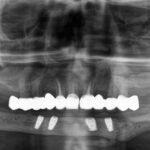

Nutzen des digitalen Workflows bei der prothetischen Rekonstruktion kompromittierter und gesunder Patienten

Prof. Dr. Dr. Walter Lückerath, Bonn